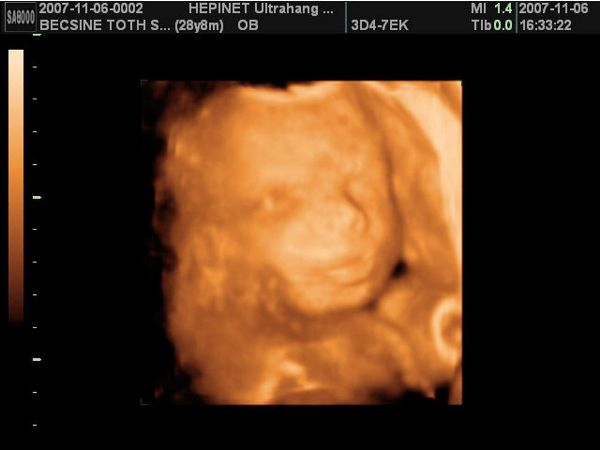

2007.11.08 16:23